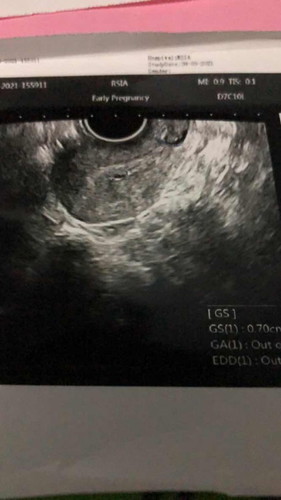

Dokter saya izin untuk bertanya, Hpht saya 2 september 2021. Lalu saya tespack urin di pagi hari ada garis samar. Terus saya coba ke bidan terlihat kantung, untuk memastikan lagi saya ke dokter spog dan terlihat kantung GS 0,70cm. Namum setelah tes urin lab hasilnya negatif. Di hasil USG transvaginal nya pun GA out off range. Mohon doker penjelasan nya saya bingung banget #ingintahu #pleasehelp #firstbaby #hamilsehat #hamil4minggu #CariTeman ##ingintahu #pleasehelp #firstbaby #firstbaby #ingintahu